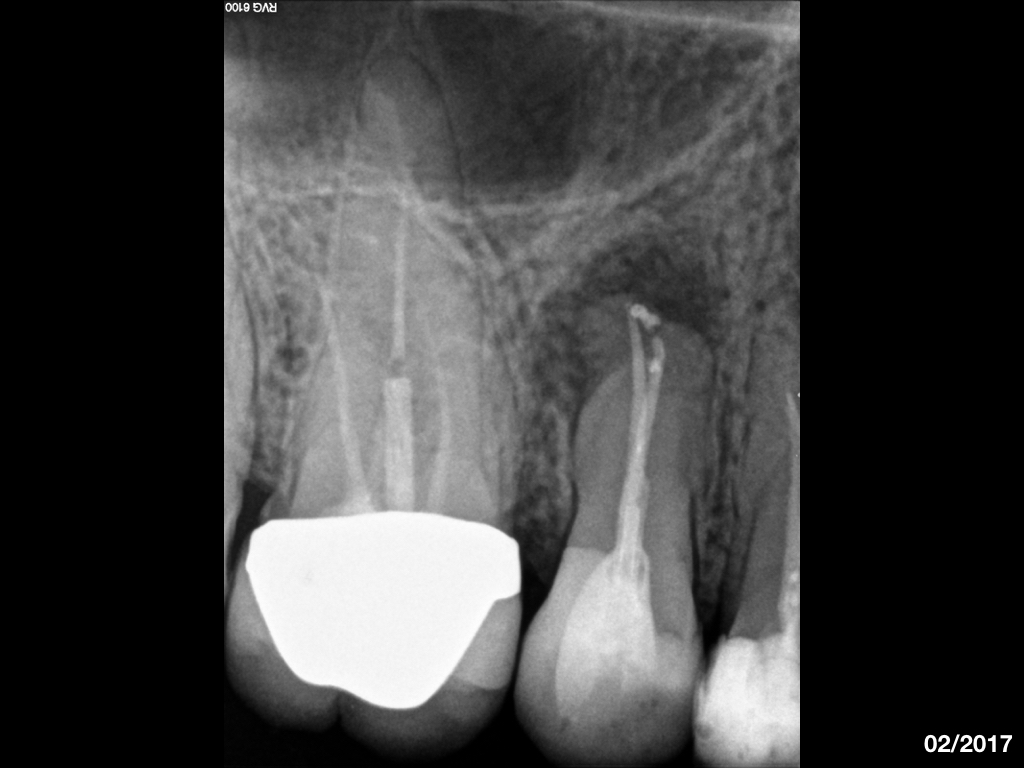

WS8593.002 Veröffentlicht 18. Juli 2019 am 1024 × 768 in Recall und Verlauf eines endodontischen Falles